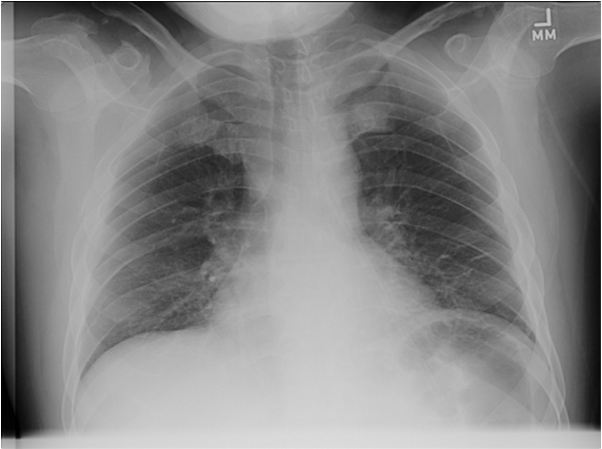

Radiographic Studies

Figure 1: Chest radiograph on admission to our hospital